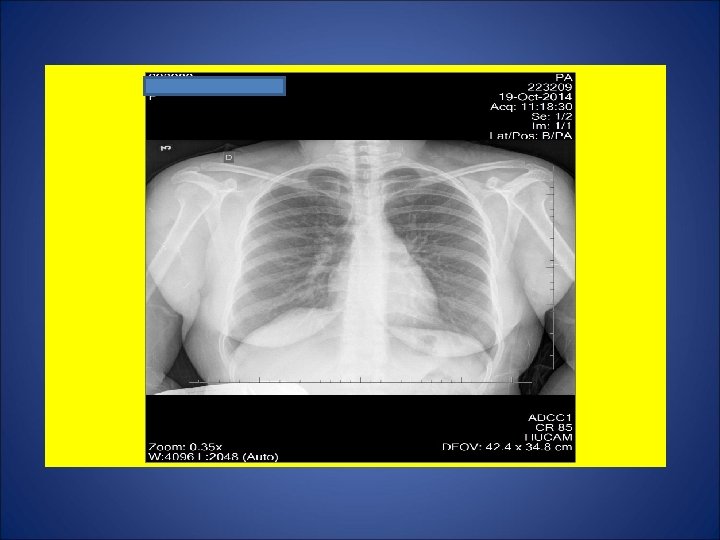

CASO 2, feminina, 37 anos de idade, auxiliar de serviços gerais, natural de Governador Valadares, residente em Cariacica (ES). Por volta de 04 Out 14, procurou P. A. devido a tosse não produtiva, febre, sudorese, calafrios, cefaléia e diarréia há 2 semanas. Foram prescritos algumas medicações (incluido antimicrobiano). Relatou perda de 4 Kg e hiporexia durante as últimas 3 semanas. Remissão da febre, sudorese e calafrios há 1 semana. Em 11 Out, procurou de novo o P. A. devido à ausência de melhora clínica. Foi internada devido ao diagnóstico de derrame pleural à direita, sendo iniciados ceftriaxone 2 g/dia e oxacilina 1 g E. V. 4/4 h. Em 15 out, foi transferida para a enfermaria de Pneumologia do Hospital Universitário para propedêutica de derrame pleural. Negou Tuberculose prévia. Contato intra-domiciliar (mesma cômodo e mesma cama) durante os últimos 14 anos com seu marido em tratamento para tuberculose pulmonar (5º mês). Tabagista e etilista. Dependência química prévia por 1 ano (maconha, cocaína e crack). HIV negativa. Ex. físico: Estado geral regular, P=61 Kg, Alt=1, 68 m, IMC= 21, 6 Kg/m 2. Propedêutica respiratória compatível com derrame pleural.

ESCARROS INDUZIDOS: 1º) 17/10/14: 1 m. L – MUCÓIDE – 55 min: BAC NEG – CULT em curso 2º) 20/10/14: 10 m. L – SALIVA – 40 min: BAC NEG - CULT em curso 3º) 21/10/14: 6 m. L – SALIVA – 46 min: BAC NEG – CULT em curso 4º) 22/10/14: 11 m. L – SALIVA – 50 min: BAC NEG – CULT em curso 5º) 23/10/14: 10 m. L – MUCÓIDE – 1: 10 min: BAC NEG – TRM: M. tuberculosis DETECTADO – CULT EM CURSO